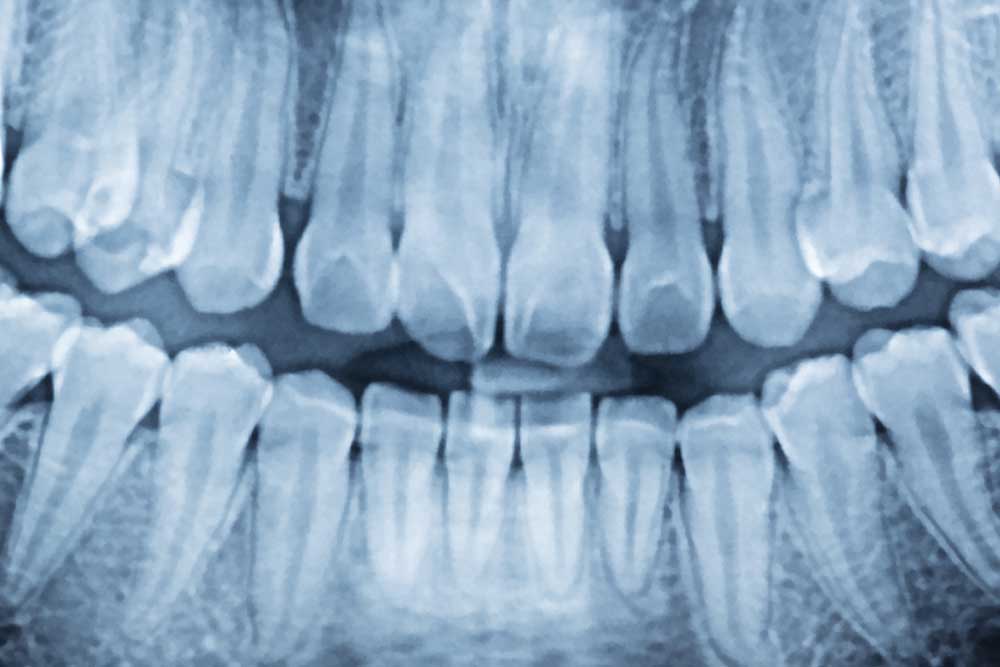

Digital X Rays Austin Texas Austin City Dental

What Digital X-Rays Reveal

Digital x-rays are an essential part of preventive and general dentistry because they help us identify:

• Cavities hidden between teeth

• Infections in the bone

• Bone loss caused by gum disease

• Impacted teeth (such as wisdom teeth)

• Abscesses, cysts, or other abnormalities

• Tooth root and jaw structure health